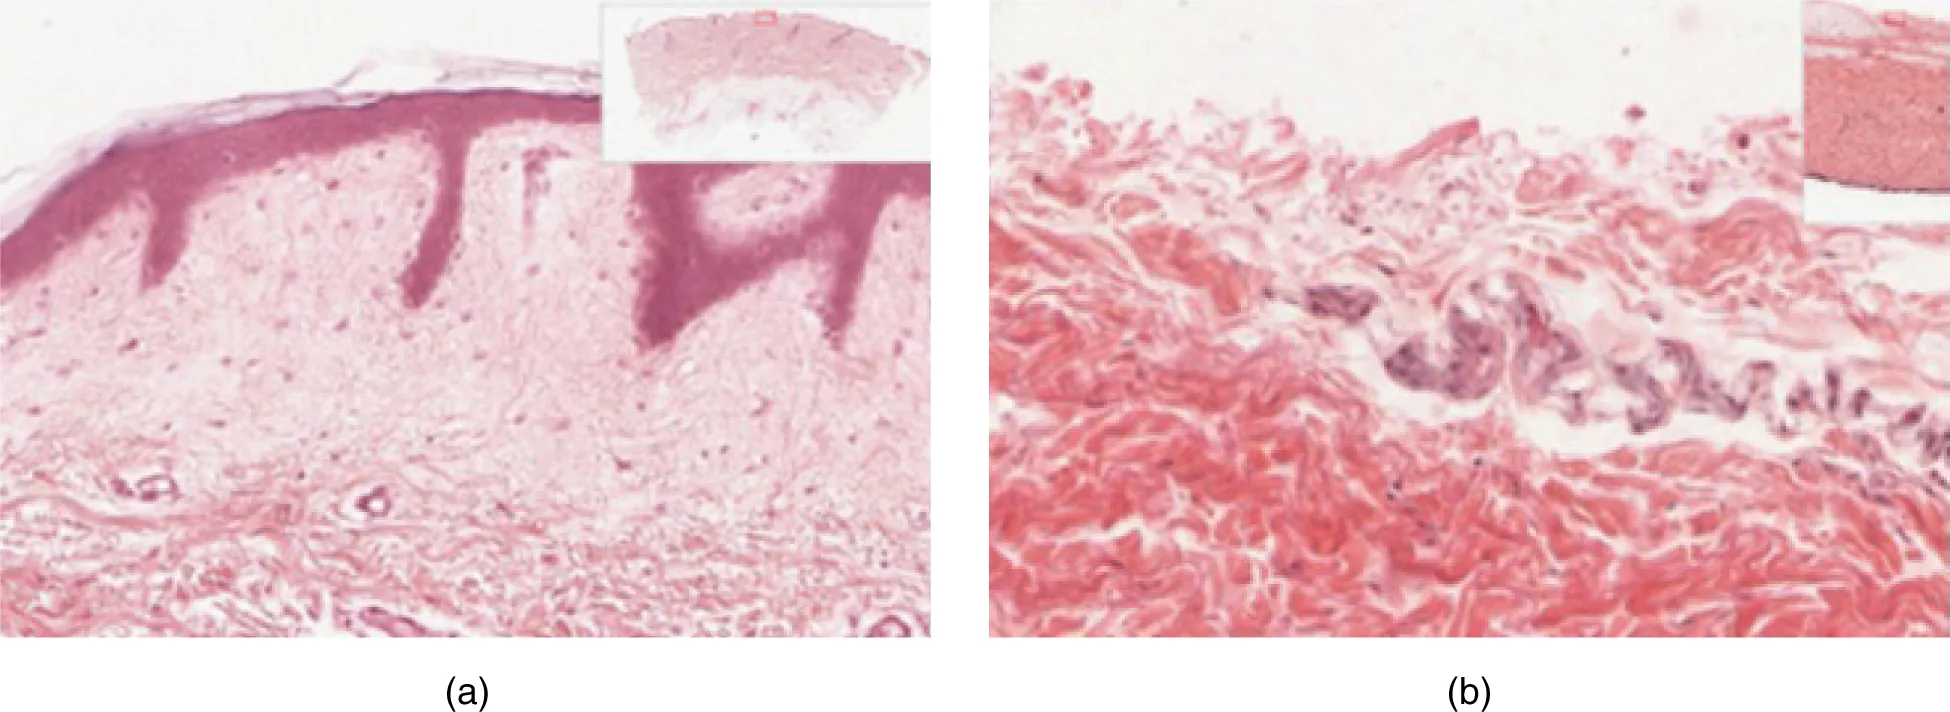

Part A is a micrograph showing a cross section of thin skin. The topmost layer is a thin, translucent layer with irregular texture and areas where cells are sloughing off. The deepest layer is dark purple and extends into the third layer with finger like projections. The third light purple layer contains thin bands of fibers and small, dark cells. The fourth, and deepest layer, is darker than the third layer, but is still light purple. It contains thick fiber bands that are loosely packed. Part B is a magnified view of the epidermis of thick skin. It shows the topmost layer is five times thicker than the topmost layer of thin skin. The topmost layer of thick skin is also denser and less translucent than the topmost layer of thin skin.

Figure 5.3 Thin Skin versus Thick Skin These slides show cross-sections of the epidermis and dermis of (a) thin and (b) thick skin. Note the significant difference in the thickness of the epithelial layer of the thick skin. From top, LM × 40, LM × 40. (Micrographs provided by the Regents of University of Michigan Medical School © 2012)